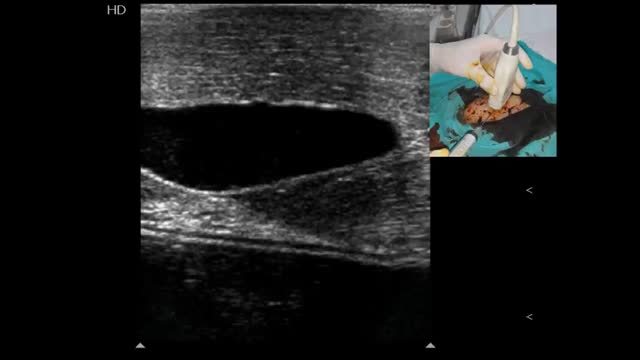

Ultrasound-guided vascular cannulation: the procedure itselfStatic vs real-time techniquesOnce a target vessel is selected, cannulation can be executed using an static technique (US-guided vascular location and skin marking but without using real-time US guidance) (Video 1) or using a dynamic or real-time technique, consisting in observing the screen for direct or indirect signs of the needle entering into the vessel.2,7 (Videos 2, 3 and 4). Both US techniques are more successful for cannulation in comparison with the landmark technique.2,7 When comparing the static and dynamic techniques, the latter has demonstrated a better performance for vascular cannulation compared to the former.2,7 Advantages of the static technique is that it does not require sterile covers for the probe or a needle-screen coordination by the operators. On the other hand, in the real-time technique, cable and probe protection (as well as using sterile US gel) is needed to maintain a sterile technique, the latter usually resulting in some loss of resolution. Additionally, dynamic techniques require a perfect coordination between needle insertion, screen observation and the evaluation of blood returning from the needle, skills that necessarily require proper training and learning curve.

In short axis cannulation, the vessel is centered on the screen and the needle is inserted in the middle, as close to the transducer as possible, and is advanced intersecting the ultrasound beam as shallow as possible to enhance needle visualization (see below). Since the tip of the needle commonly exceeds the body of the transducer as is inserted, observing the needle tip is difficult; in fact, the body of the needle (or its derived reverberation artifacts) is the portion seen7,11 (Fig. 5A). This explains why this technique is usually considered an “out of plane” technique. When using this approach, indirect signs of cannulation are important, such as the movement of the superficial tissues and the flattening of the anterior vessel wall as the needle is advanced into the vessel.

In the long axis technique, the needle follows the path of the transducer and the ultrasound beam; therefore, it is completely visualized, including the bevel, advancing from the superficial tissues (using the ski lift technique and a shallow insertion angle, see below) up to its definite position into the vessel7,8,11,12 (Fig. 5B). This is why this technique is commonly considered an “in plane” technique. Using the probe orientation mentioned above, the needle is observed as is advanced from the right side of the screen; however, individual practitioners may prefer to see the needle from the other side (this can be achieved by changing the probe orientation or simply inverting the indicator probe positioning in the screen without changing the probe orientation).

Using the oblique technique, the needle is usually advanced using an “in plane” approach10 (Fig. 5C).

Confirming proper vessel cannulationAlong with detecting direct and indirect signs of vessel cannulation and observing blood returning, it is recommended to have the guidewires shown into the target vessel when used2,7 (Video 7). This practice allows to finally advance the catheter into the target vessel and not in adjacent tissues if it is unintentionally placed in a wrong position. The final position of the catheter should also be directly and indirectly displayed (Video 8).2,7 In peripheral venous cannulation, an agitated saline flush (10ml) passed through the catheter allows to display microbubbles running into the vessel and thus guaranteeing its adequate position and function7 (Video 8). For central venous cannulation, an agitated saline flush is injected through the catheter, normally observing the microbubbles flowing in the right atrium7 within 1–2s16 in simultaneous echocardiographic assessment in subcostal or apical 4-chamber views, performed with a phased-array or a convex probe.